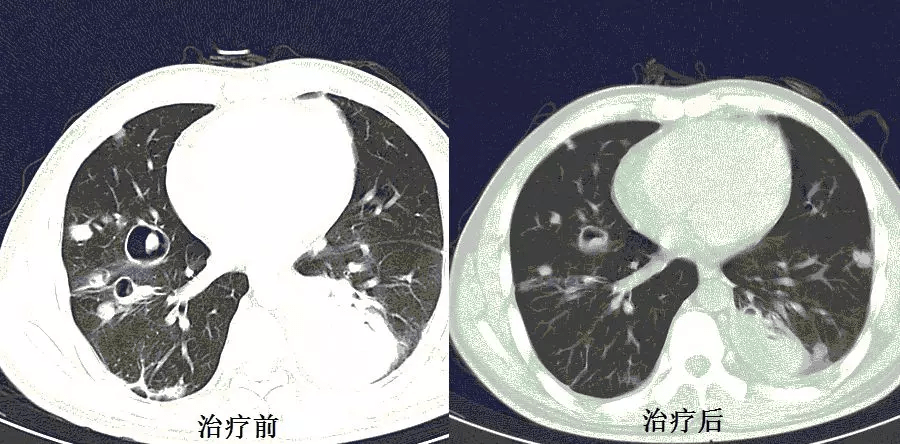

CT:双肺多发空洞、气囊、结节 , 病灶以胸膜下为主 , 见实变 , 胸腔积液 。 肝脓肿 。

CT也提示脓毒肺栓塞!金葡菌?

这个患者的特点是 肺空洞、肝脓肿!肝脓肿的存在 , 大大缩小了诊断范围 , 缩小了细菌范围!肺CT提示脓毒肺栓塞 , 并且同时存在肝脓肿 , 绝大多数都是肺炎克雷伯杆菌 , 不是金葡菌 , 真菌更是少见!

送检脓液培养出:肺炎克雷伯菌 。 抗感染 , 肝脓肿穿刺引流 , 病情唰唰地好转 。